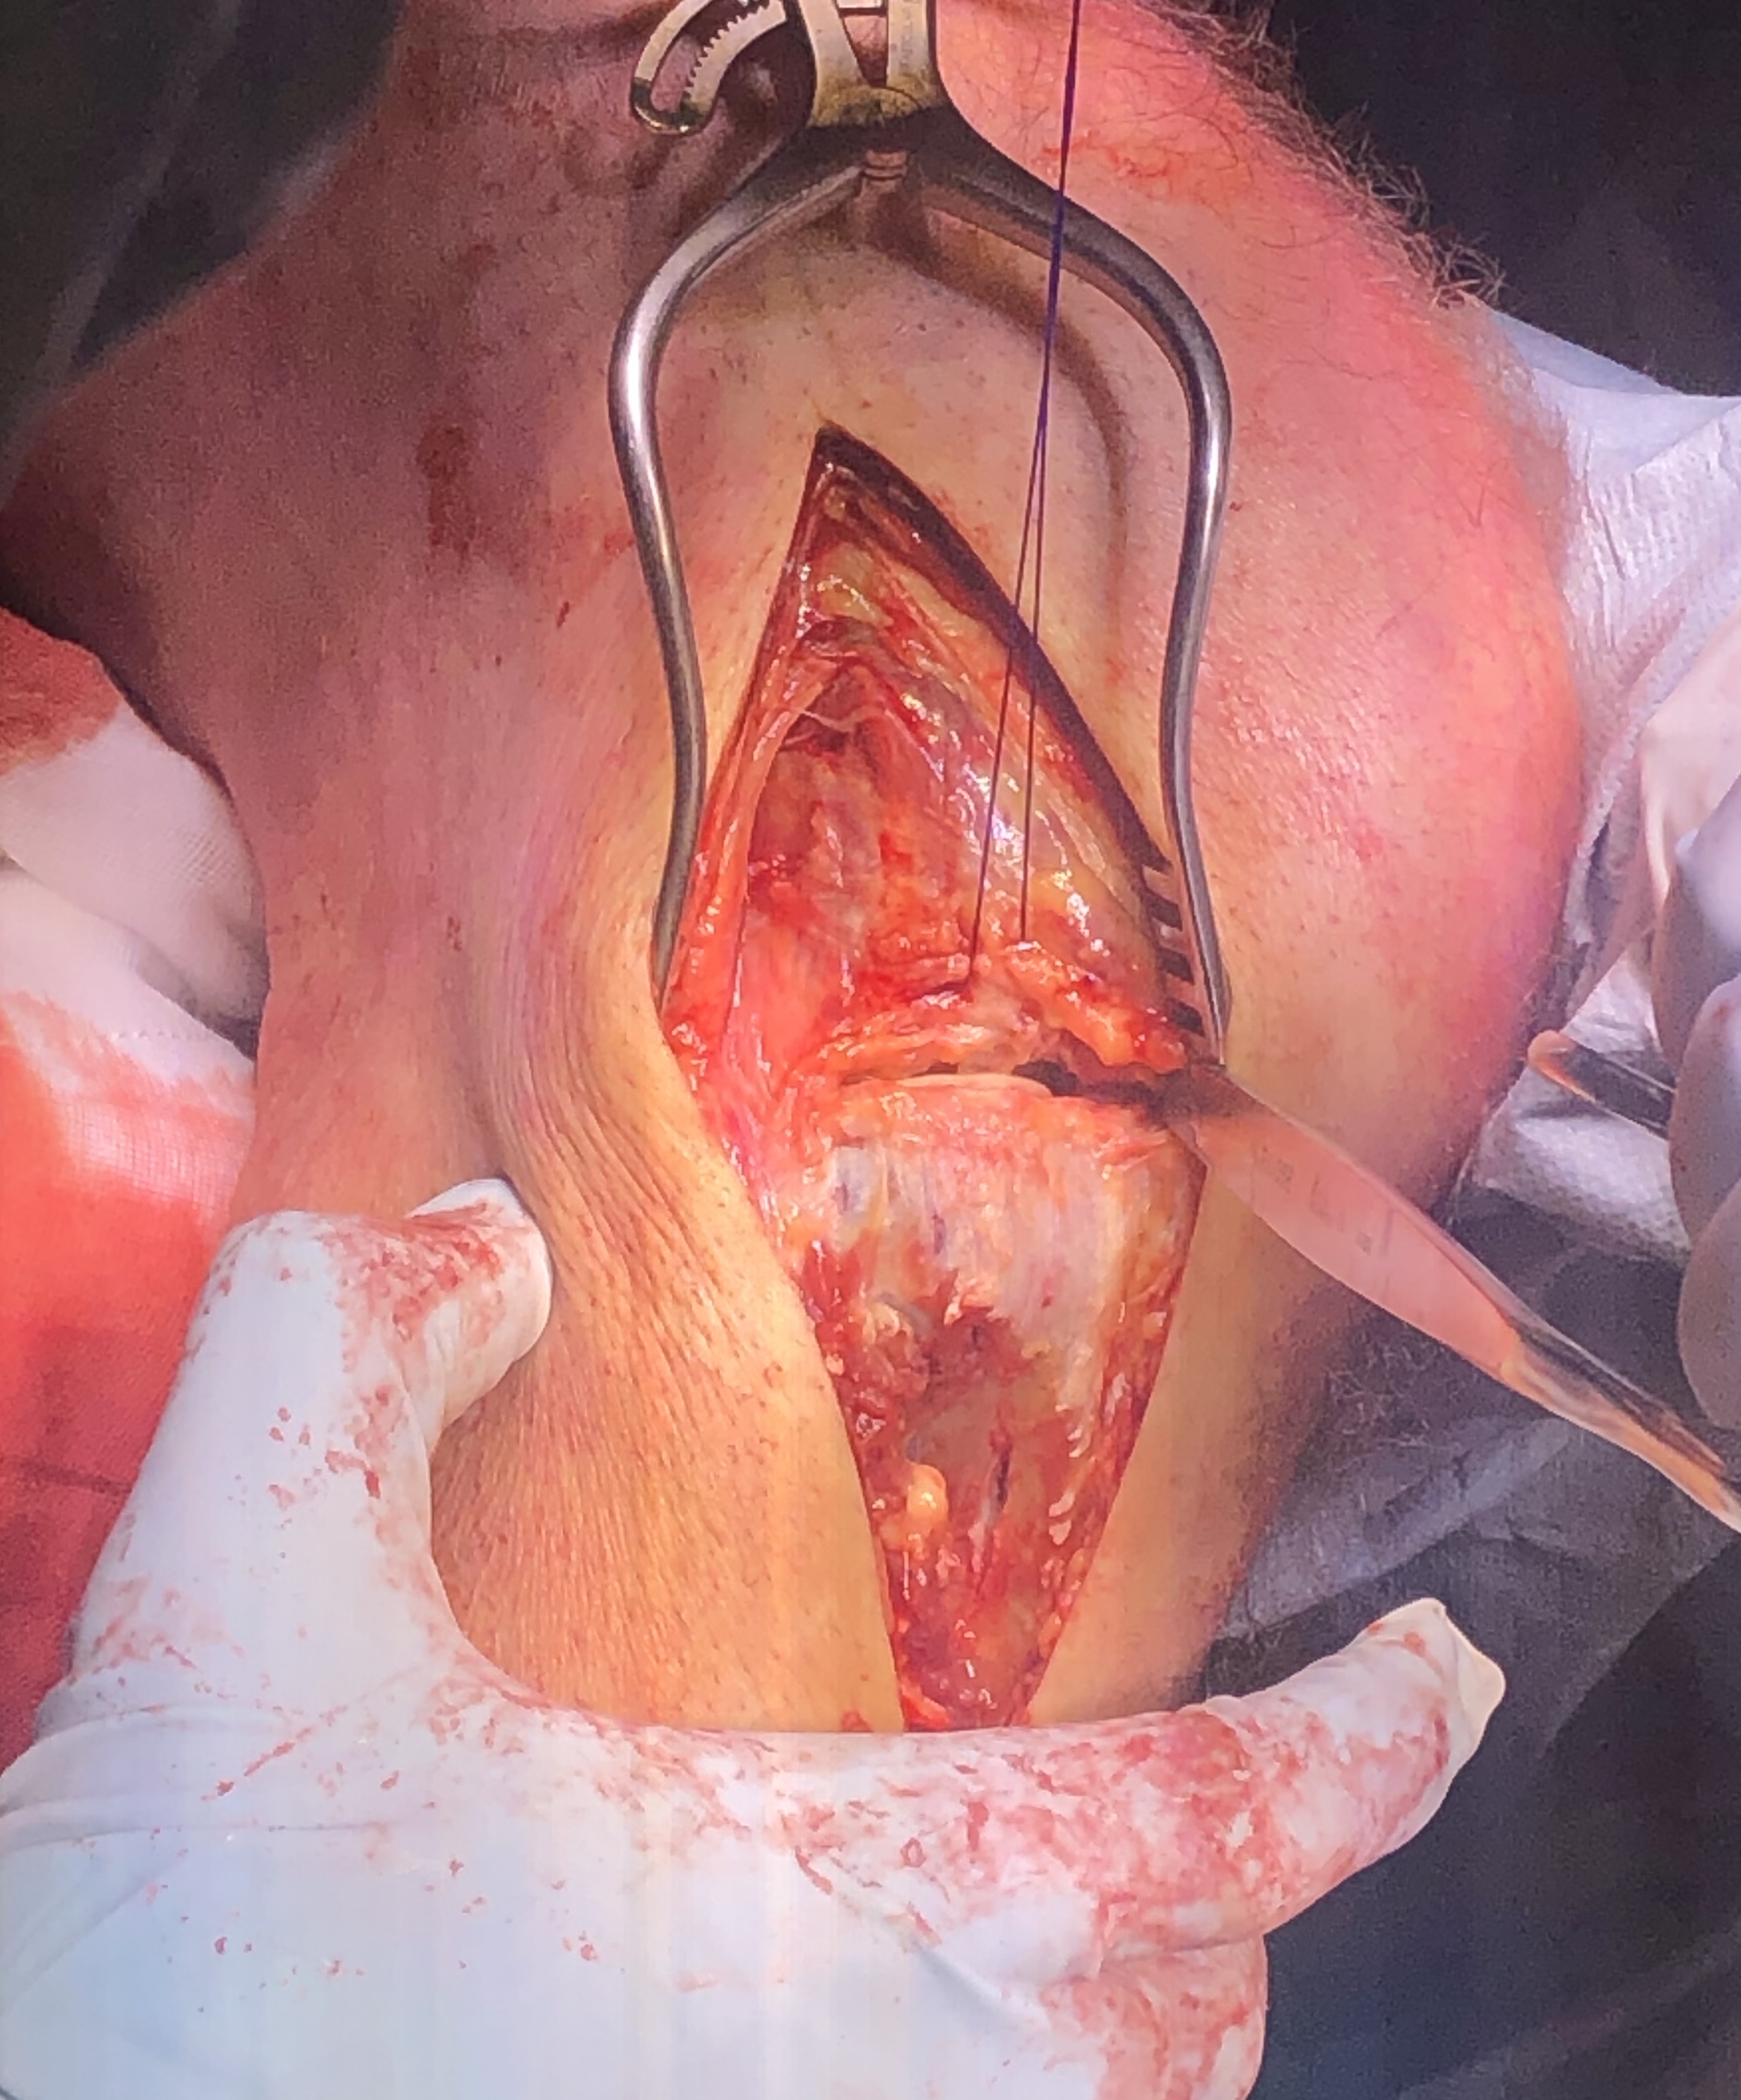

Posteromedial Tibial Plateau Fractures

Posteromedial approach and buttress plate

- Burks modified posterior approach

- put leg over triangle, can let let flop out to get to medial side

- incision based upon posteromedial tibia

- interval between semimembranosus and medial head of gastrocnemius

- medial head of gastrocnemius retracted laterally

- hamstring tendons retracted medially

- place blunt homann gently across back of tibia to expose fracture

- subperiosteal release of the popliteus muscle

- place posterior anti-glide buttress plate